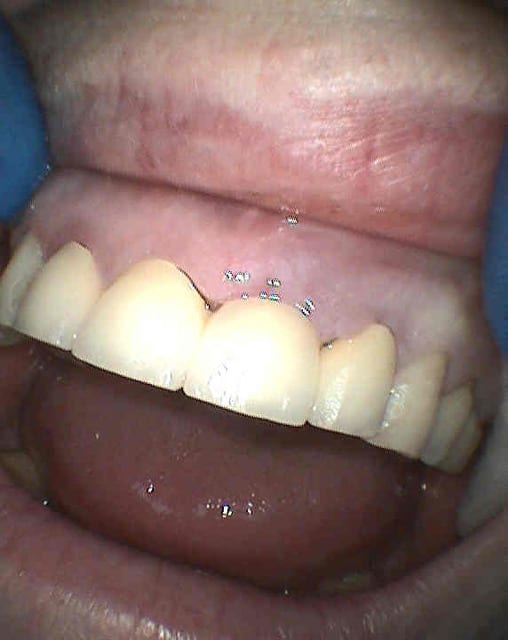

oui, car le but ici est esthétique ( des couronnes unitaires, c'est plus joli qu'un bridge)

NB: sur les dents voisines on voit des provisoires réalisées le jour même pour me guider dans le positionnement tridimensionnel de l'implant, en aucun cas ce ne sont les provisoires d'usage.)

je vous laisse les clichés.

sur les photos, la gauche et la droite sont inversées